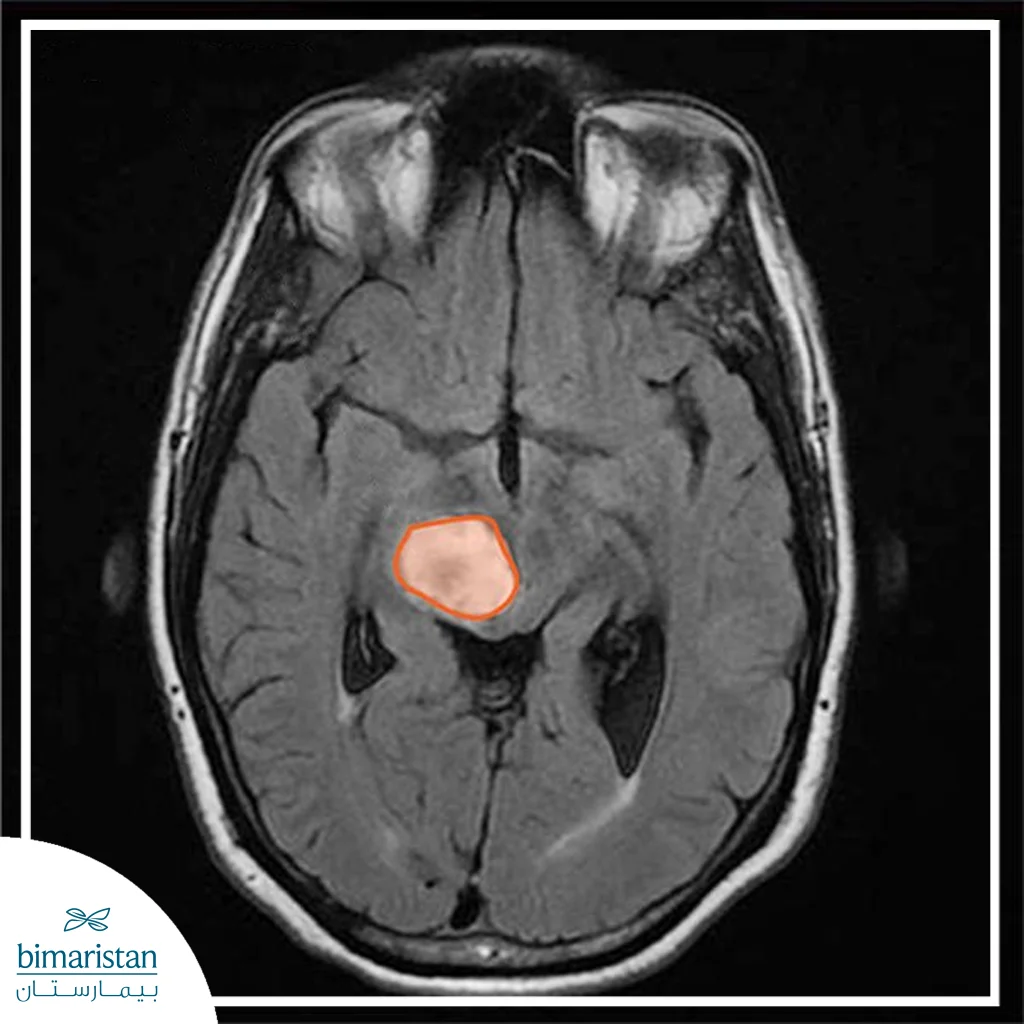

- Imaging tests: Magnetic resonance imaging (MRI) helps detect a brain tumor.

- Collecting and examining a sample of abnormal tissue from the tumor (biopsy).